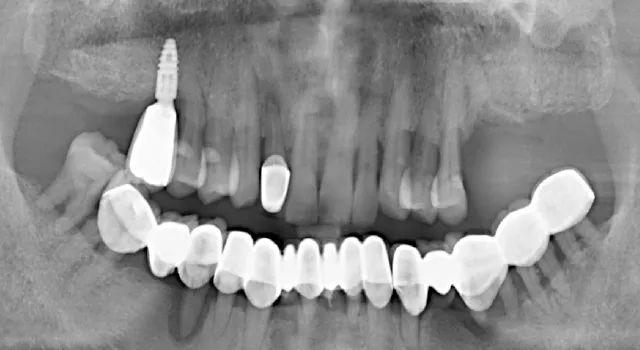

無獨(dú)有偶,一起看看那些價格便宜但醫(yī)療質(zhì)量不過關(guān)的種植牙:劣質(zhì)種植體導(dǎo)致的種植牙失敗

手術(shù)失敗的種植牙,使用壽命僅僅只有2個月(種植窩空虛,頰側(cè)嵴頂骨缺損)